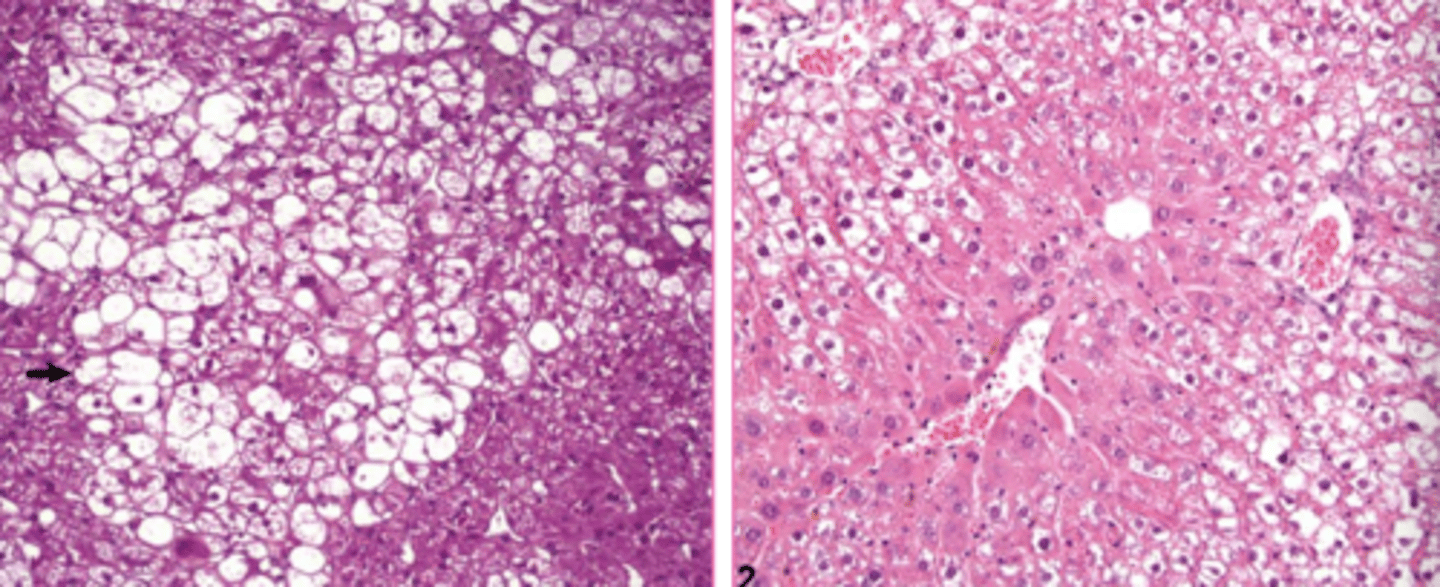

globoid cell leukodystrophy

What?